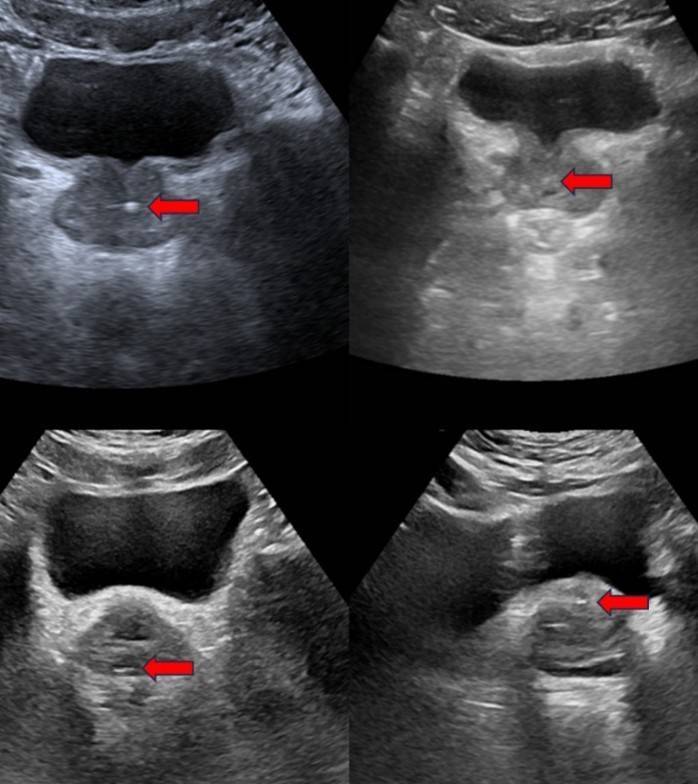

图1:超声影像中不同类型前方腺钙化的施展(箭头处)